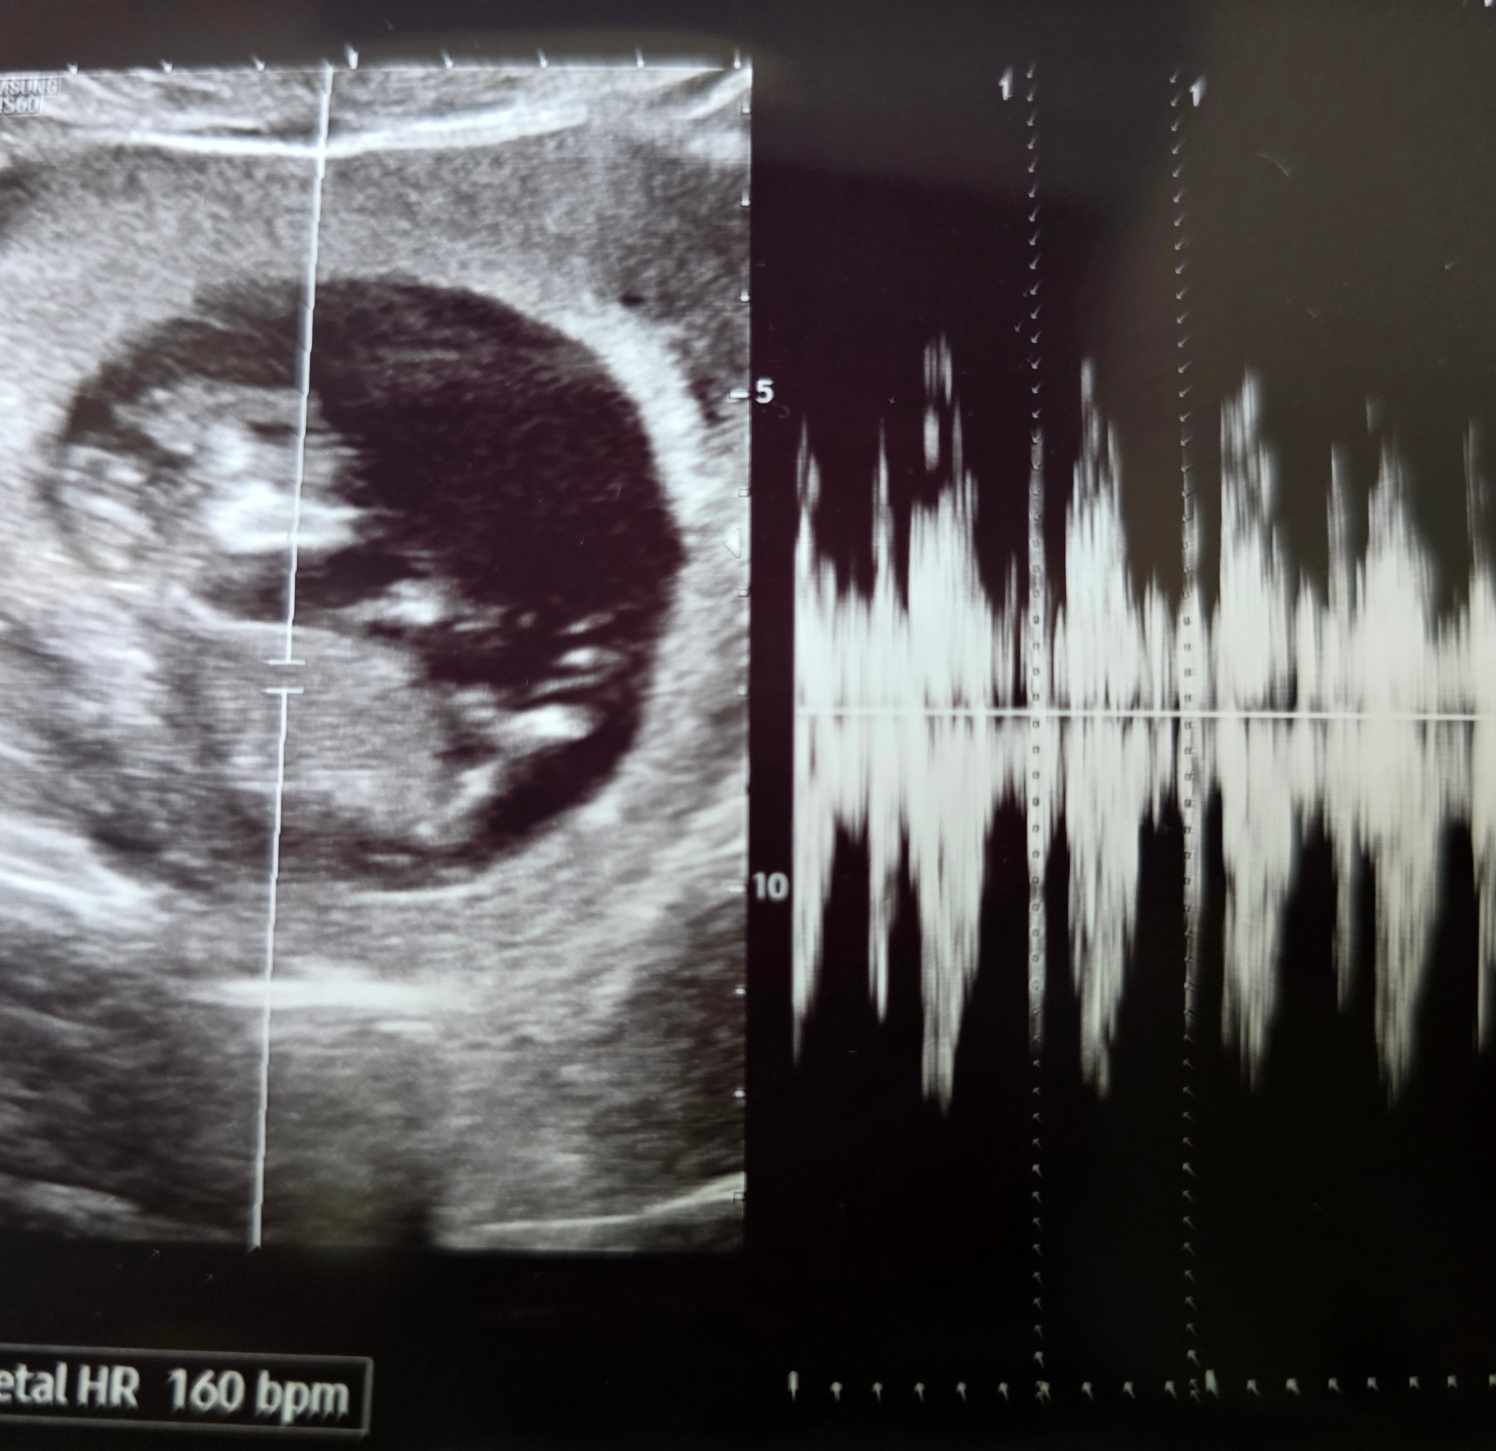

그리고 아기 심장소리까지 들었다!!!!

크기는 4일 작지만 따라가기도 하고 착상이 조금 늦었다 생각하면 이대로 유지만 해도 괜찮을 거라고 말씀해 주셨다!!

아기 3일 전에 봤는데 딱 3일만큼 잘 커있고 아기 심장도 쿵쾅쿵쾅 잘 뛰니까 걱정 말라고 해주셨다.. 휴..

7주 2일엔 난황이랑 비슷한 크기였는데 7주 6일엔 난황보다 커졌다!!!

뚝딱이 크기는 7주 2일 크기로 4일 작게 꾸준히 잘 크고 있었다!!ㅎㅎ

지난주까진 4일씩 느렸는데 10주 6일 차엔 이틀 느린 10주 4일 차 크기!!

뚝딱이는 12주 2일 크기로 다 따라잡았다!!! 너무 이쁘고 기특한 뚝딱이!!><